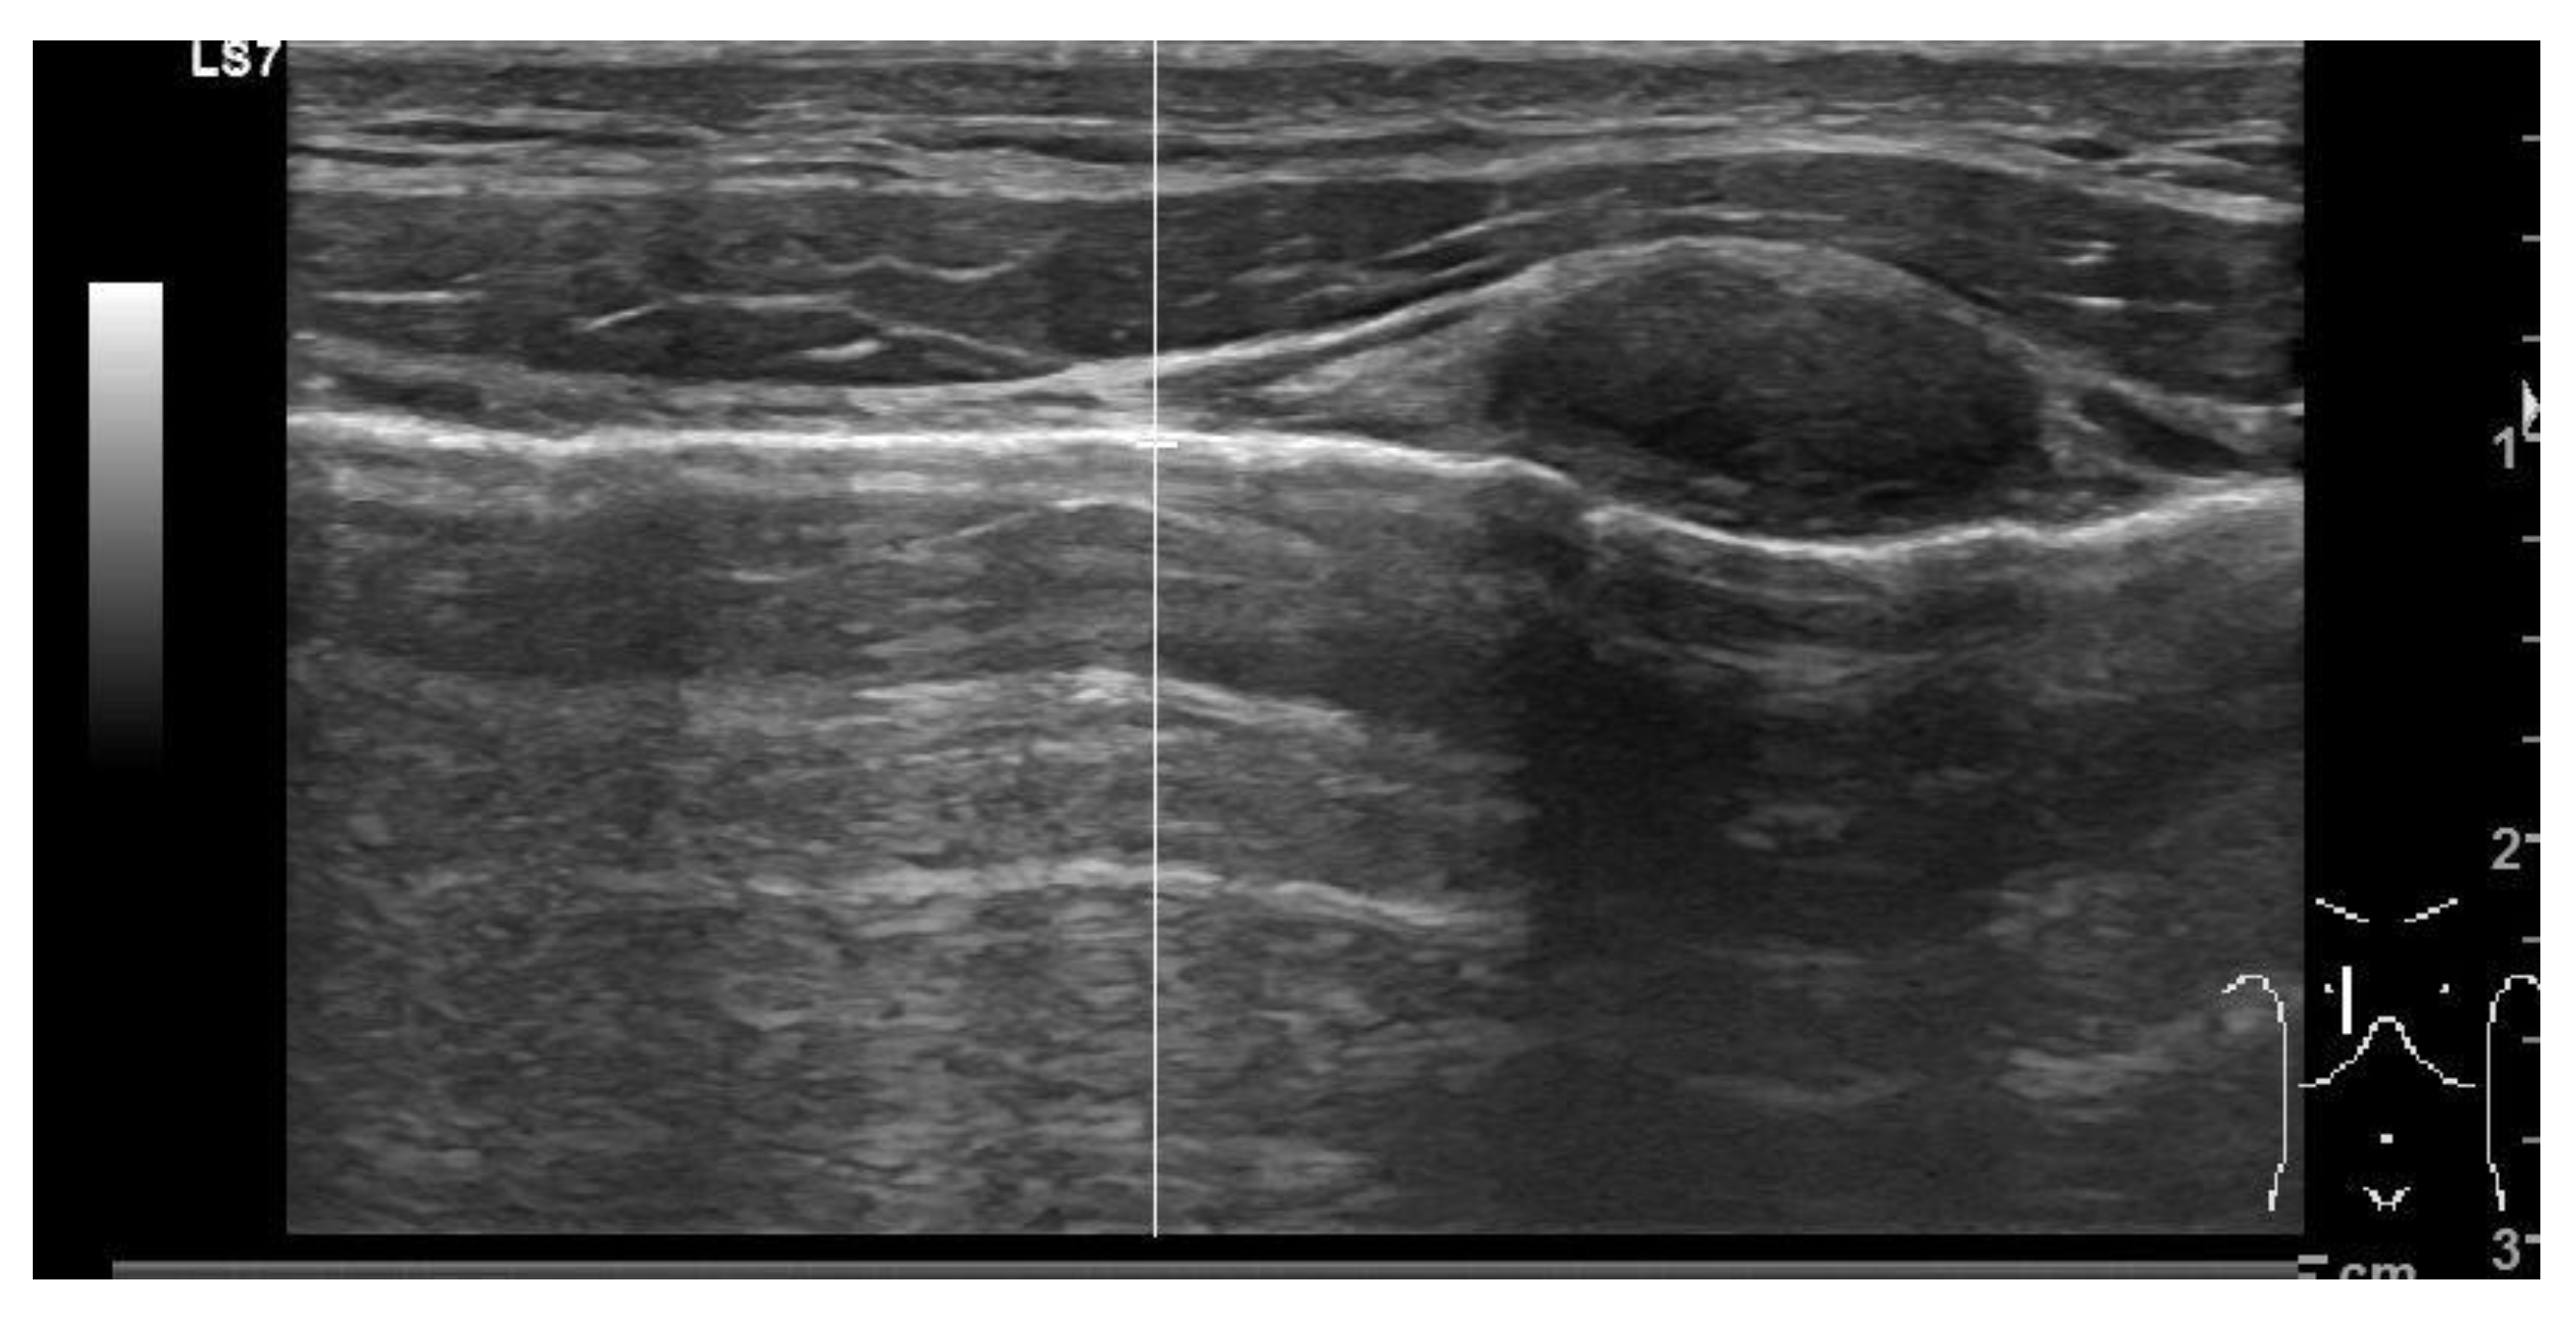

3.4.2. Tension Pneumothorax

Lung collapse and the subsequent compression of vital structures leads to decreased cardiac output and impaired blood circulation, ultimately resulting in cardiac arrest. Although clinical evaluation can raise suspicion, it is the sonographic findings that play a valuable role in aiding the rapid recognition of tension pneumothorax and drive appropriate intervention. Chest ultrasound shows high accuracy in pneumothorax diagnosis [28]. Signs suggesting the presence of this condition during cardiac arrest comprise a lack of lung sliding determining an “A profile”, as well as underfilled cardiac chambers and a plethoric inferior vena cava (Figure 4). Conversely, the presence of a lung pulse, determined by the absence of sliding but with synchronous beating of the visceral pleura with the heart, rules out pneumothorax. In severe cases, tension pneumothorax can cause a mediastinal shift, where the heart and major vessels are displaced due to pressure from the collapsed lung. Identifying these sonographic signs of tension pneumothorax during cardiac arrest is crucial for prompt diagnosis and appropriate intervention. Immediate decompression with a thoracostomy to release the trapped air can be performed as an emergency life-saving procedure [29].

Figure 4.

Ultrasound showing pneumothorax resulting in an “A profile”: horizontal artifactual repetitions of the pleural line.